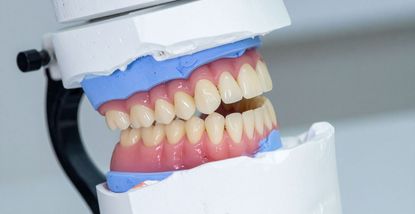

All-on-4 je tehnika ugradnje zubnih implantata kojom se cijeli niz zuba nadoknađuje pomoću samo četiri implantata po čeljusti. Na te implantate postavlja se most koji izgleda i ponaša se poput prirodnih zuba.

U istom danu, pacijentu se postavlja privremeni fiksni most, što znači da odlazi kući s novim osmijehom već nakon jedne posjete. Nakon nekoliko mjeseci, kada se implantati potpuno integriraju s kosti, izrađuje se trajni most koji savršeno pristaje i zadovoljava sve funkcionalne i estetske zahtjeve.